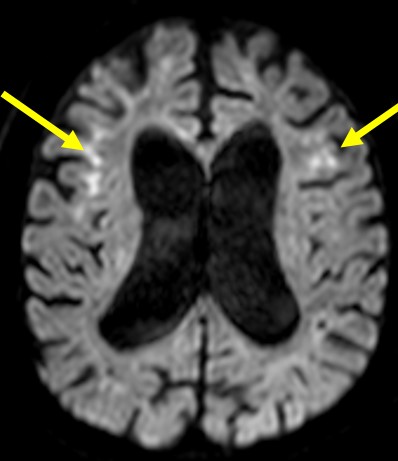

神経核内封入体病(NIID) 海馬硬化症

大脳の皮髄境界の高信号域 海馬の萎縮と高信号 T2強調像

拡散強調画像(DWI)